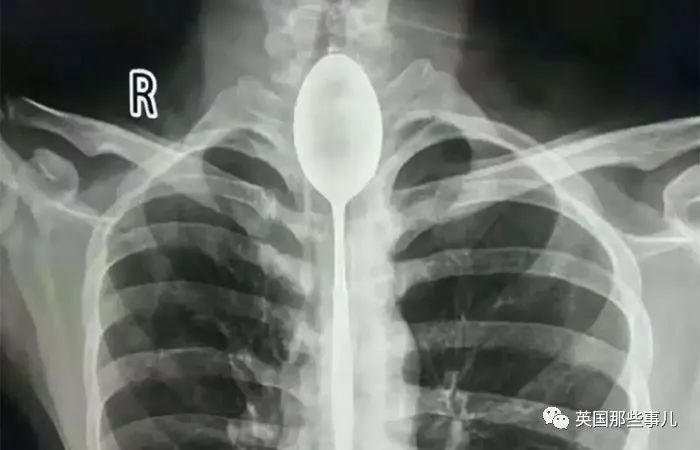

國內(nei) 一位大哥因為(wei) 跟人打賭,將勺子卡在食道一年多,但這竟沒讓他感覺明顯不適....